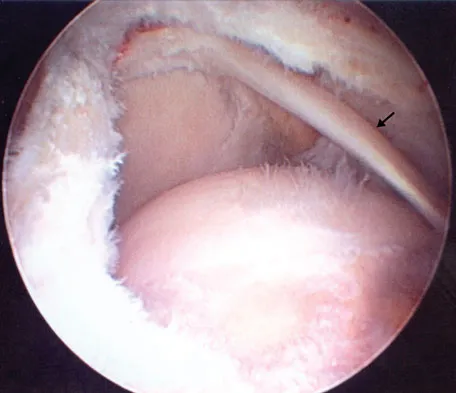

Question 91

Figure 43 shows an arthroscopic view of a right shoulder through a lateral portal in the beach chair position. The arrow is pointing to what structure?